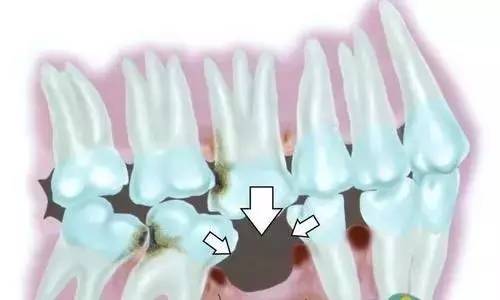

其实一颗牙齿缺失以后,对口腔健康的危害远远没有停止,它还会对两侧邻牙、对合牙、其他牙齿造成直接或间接的伤害,危害波及整个口腔。

1、邻牙松动,又掉2颗

首先,牙齿缺失后,如果不及时治疗会导致邻牙松动:牙齿缺失后,相邻的牙齿会因为没有固定的依靠,向缺牙间隙倾斜,时间长了会造成周围邻牙的松动,致使全口牙齿的正常功能遭受严重的破坏。

2、对牙伸长,再掉1颗

牙齿缺失不及时治疗会导致对侧牙伸长:由于缺牙后的间隙不能及时修复,侧牙因无咬牙合会伸长,例如下牙缺了一个牙,长期得不到修复,上面相对应的那颗牙则会有伸长现象。严重还能占据整个缺个间隙,造成牙齿无法修复,导致咬合紊乱。

3、食物嵌塞,口气根源

牙齿缺失不及时治疗会容易使食物嵌塞:正常牙齿与牙齿之间,排列得十紧密,一旦邻近的牙齿移动,牙齿与牙齿之间就会出现缝隙,容易使食物嵌塞到牙齿间隙里,从而引起口臭、龋齿、牙周病等。

4、细菌堆积,龋齿难防

牙齿缺失会引发龋齿(蛀牙):牙齿缺失会导致食物的嵌塞,这样的话食物嵌塞到牙齿间隙里,是很不容易清洁干净的,长时间的细菌堆积就会造成龋齿。